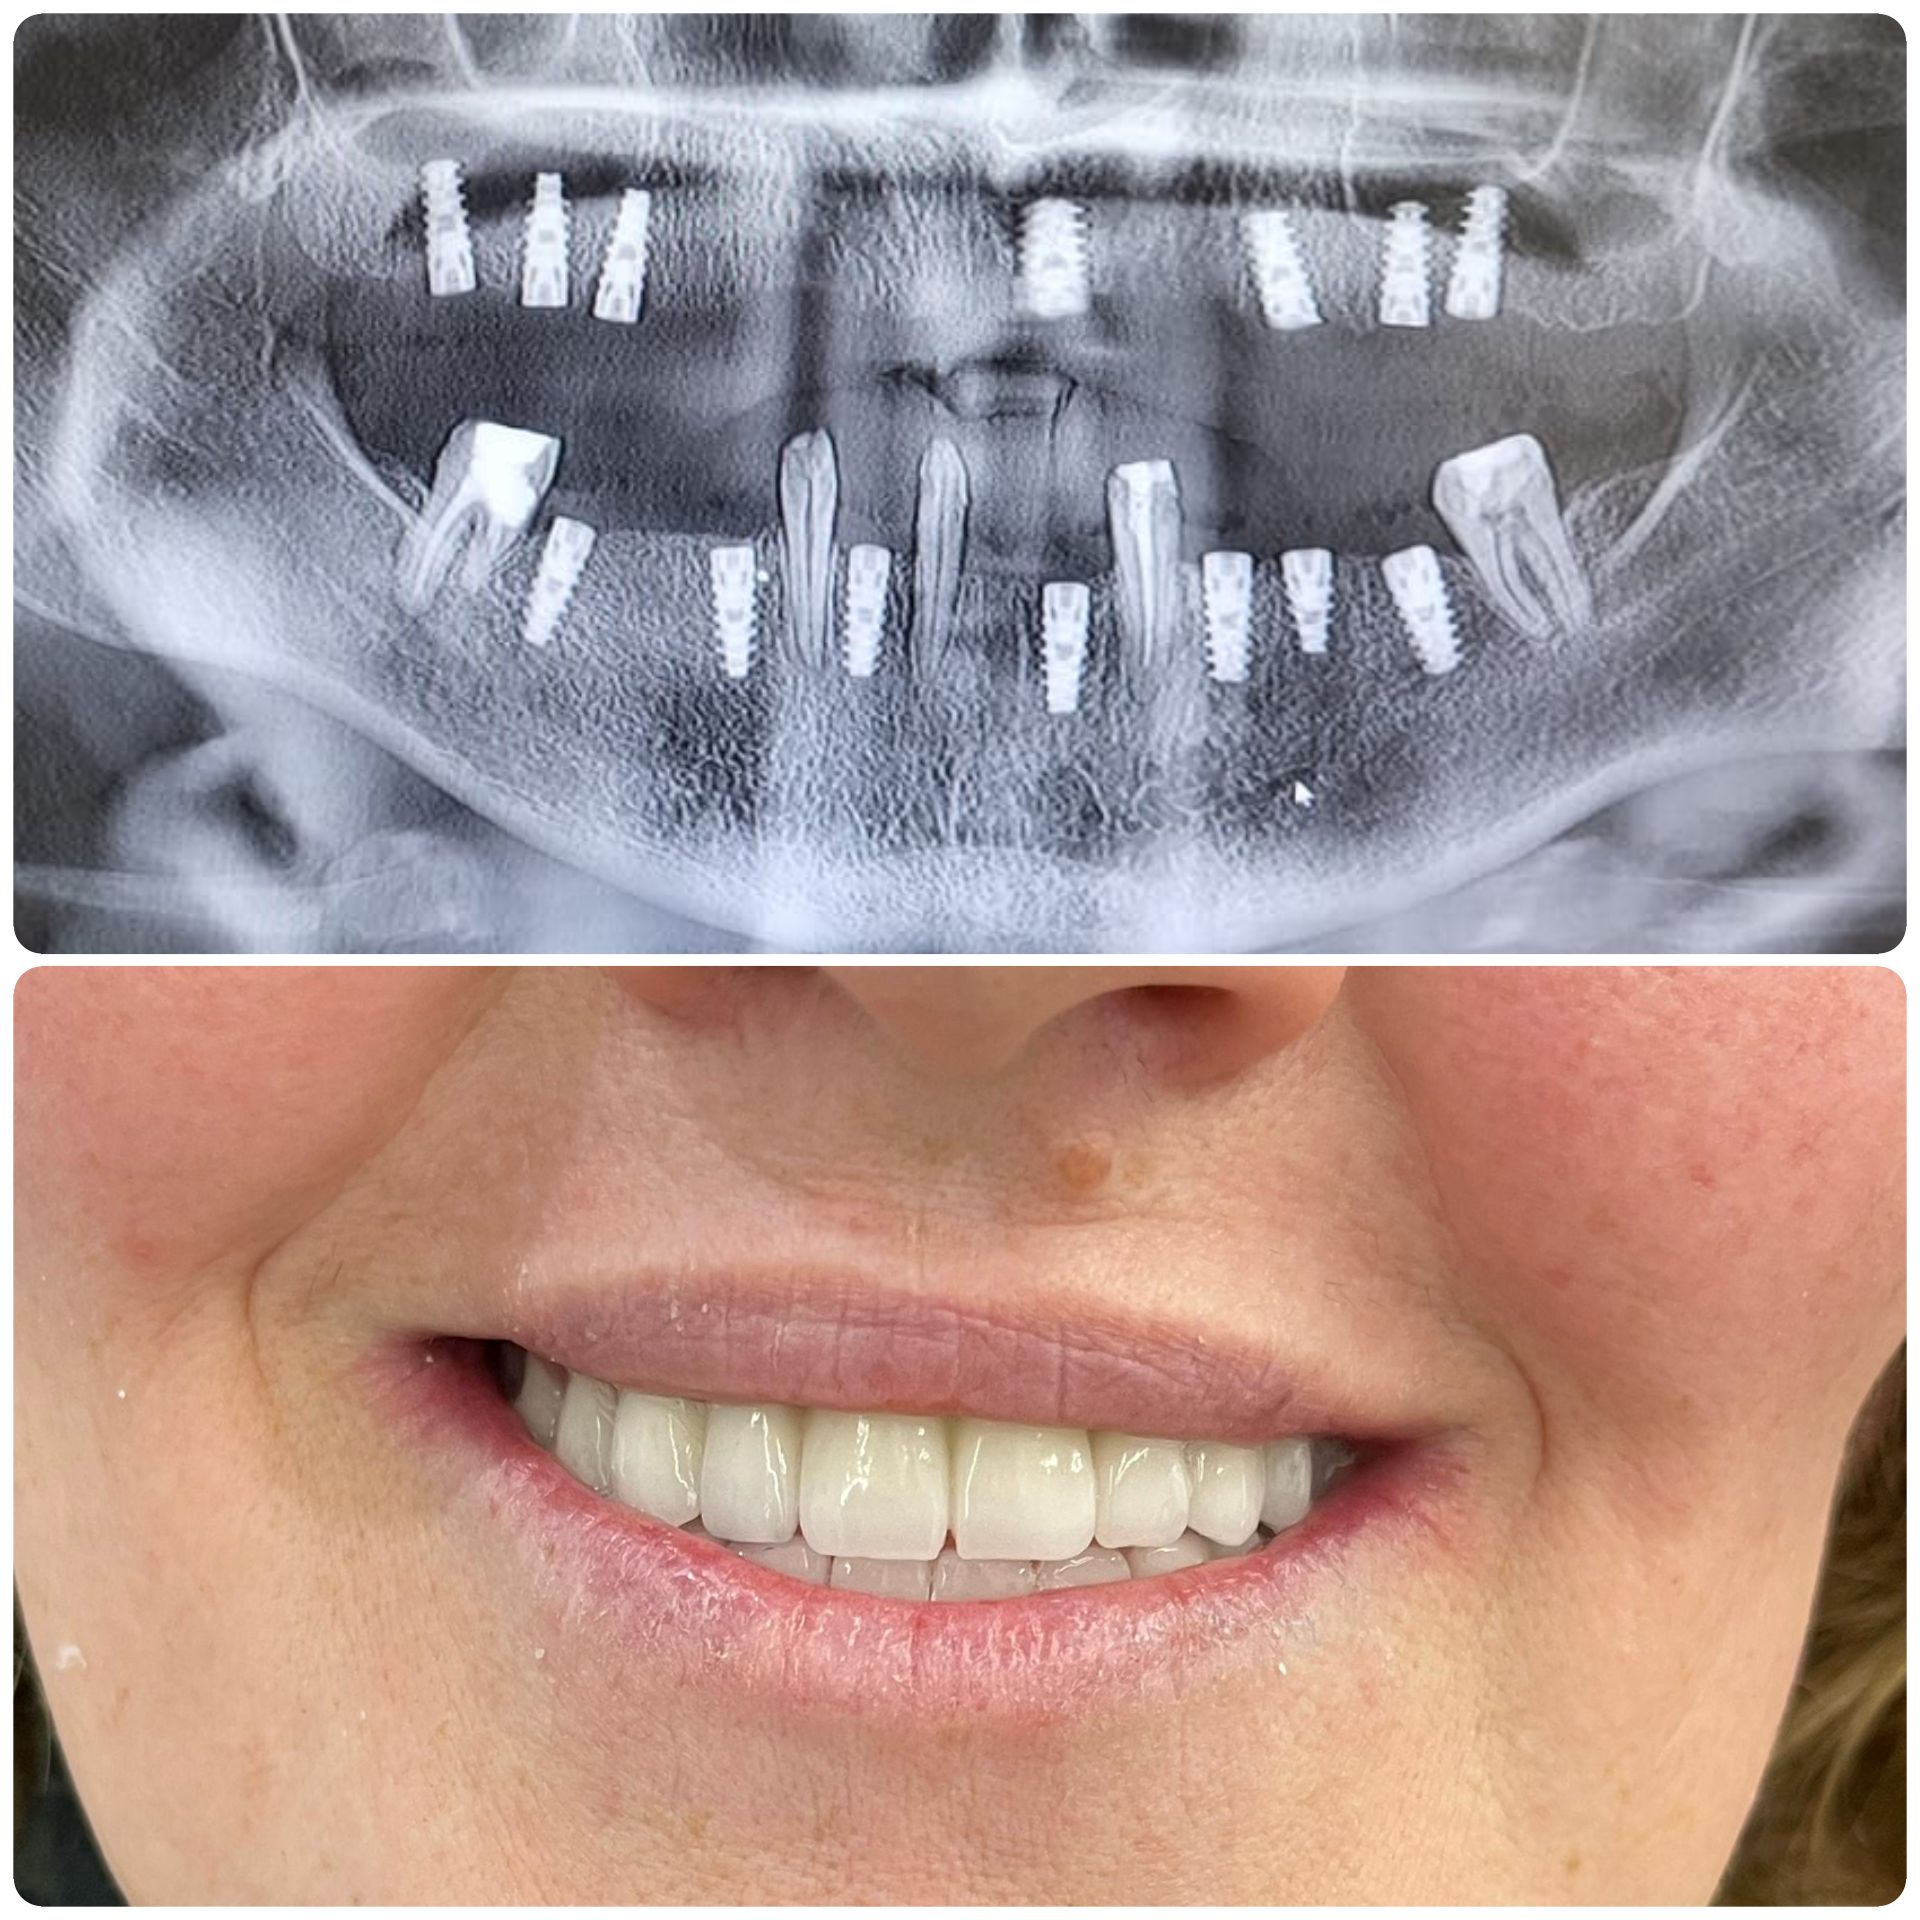

Si inizia con una consulenza e immagini 3D. Gli impianti vengono posizionati con precisione e restaurati con corone che appaiono e funzionano come denti naturali. L’intero processo è attentamente pianificato in fasi: valutazione, posizionamento dell’impianto, periodo di guarigione e restauro finale. Con le tecniche moderne, molte procedure sono minimamente invasive e spesso vengono fornite soluzioni temporanee, così da non rimanere mai senza sorriso durante il trattamento.